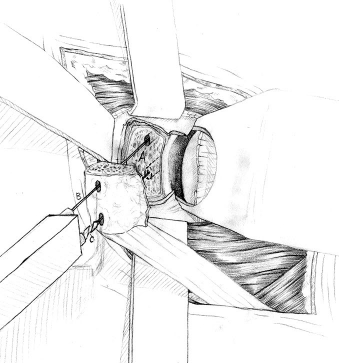

Transfer of coracoid process and conjoint tendon through subscapularis

Coracoid osteotomy

- use retractor on superior surface to identify entire coracoid

- release coracoacromial ligament from lateral coracoid

- release pectoralis minor from medial coracoid

- 2 cm coracoid osteotomy using 90o oscillating blade on microsagittal saw 100

- create bleed bone surface on posterior coracoid

- mobiize conjoint tendon, beware MCN 5 cm distal

Glenoid preparation

- split subscapularis at midsubstance of muscle belly

- can perform subscapularis tenotomy

- capsulotomy - vertical or transverse

- medial glenoid retractors / Fukuda retractor over humeral head

- inferior glenoid retractor - protect AXN

- create bleeding glenoid bone with burr

Secure coracoid

- inferior half of glenoid

- no medial overhang

- secure with 2 x bicortical screws with compression

Closure capsule / subscapularis